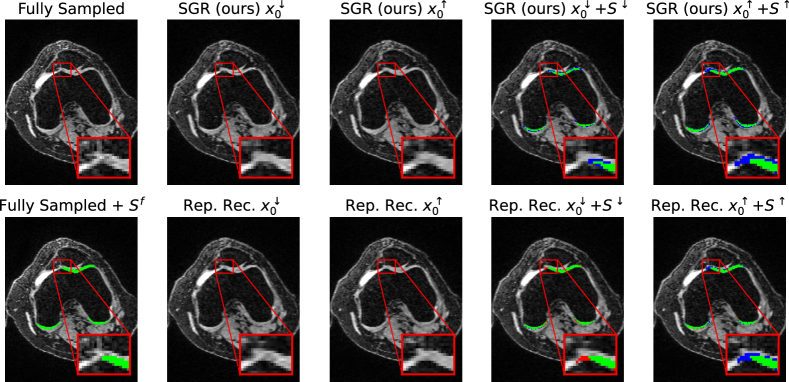

Figure 3: Sampling vs. adversarial guidance. Examples of lower- (x0superscriptsubscript𝑥0x_{0}^{\downarrow}) and upper-bound (x0superscriptsubscript𝑥0x_{0}^{\uparrow}) reconstructions (16x acc.) and segmentations (Ssuperscript𝑆S^{\downarrow}, Ssuperscript𝑆S^{\uparrow}) using our SGR method and the standard RR method. (Sfsuperscript𝑆𝑓S^{f} is the segmentation of the fully-sampled image. Green: Sf&Ssuperscript𝑆𝑓superscript𝑆S^{f}\&S^{\uparrow} or Sf&Ssuperscript𝑆𝑓superscript𝑆S^{f}\&S^{\downarrow}, Blue: Sf>Ssuperscript𝑆𝑓superscript𝑆S^{f}>S^{\downarrow} or Sf<Ssuperscript𝑆𝑓superscript𝑆S^{f}<S^{\uparrow}, Red: Sf<Ssuperscript𝑆𝑓superscript𝑆S^{f}<S^{\downarrow} or Sf>Ssuperscript𝑆𝑓superscript𝑆S^{f}>S^{\uparrow})

We perform experiments on 4 acceleration factors: 4×4\times, 8×8\times, 12×12\times, and 16×16\times, analyzing the behavior of the uncertainty boundaries of SGR and RR. We assess the quality of the generated segmentations Ssuperscript𝑆S^{\downarrow} and Ssuperscript𝑆S^{\uparrow} by calculating the precision for Ssuperscript𝑆S^{\downarrow}, recall for Ssuperscript𝑆S^{\uparrow} and the uncertainty volume Vuncsubscript𝑉𝑢𝑛𝑐V_{unc}. We focus on precision on Ssuperscript𝑆S^{\downarrow}, as we want to avoid overestimating the segmentation and creating false-positives, and measure recall for Ssuperscript𝑆S^{\uparrow}, because we want to avoid segmentations containing false-negatives. An example image where RR overestimates Ssuperscript𝑆S^{\downarrow} while our method predicts accurate boundaries is shown in Fig. 3. A similar observation can be found in Fig. 5, where our method sustains high precision and recall values, while these scores degrade with higher acceleration for the baseline method RR. Reconstruction quality as measured by SSIM and PSNR remains very high for SGR compared to RR, as shown in Tab. 1.